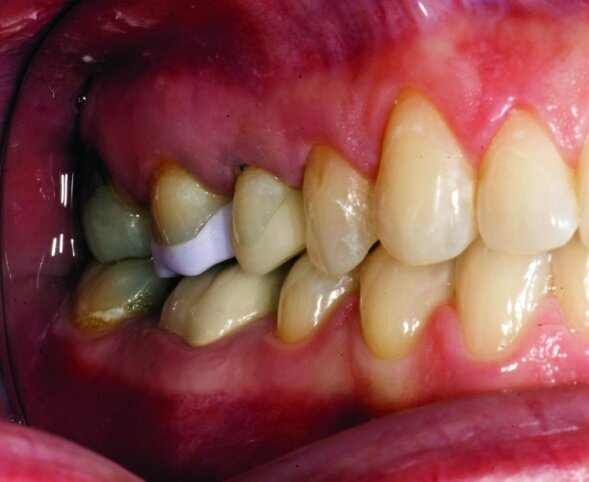

The final result was minimally invasive restorations that appear and function naturally, while decreasing risk of tooth fracture, and minimize further risk to the teeth. (Figs. 35a–36b).